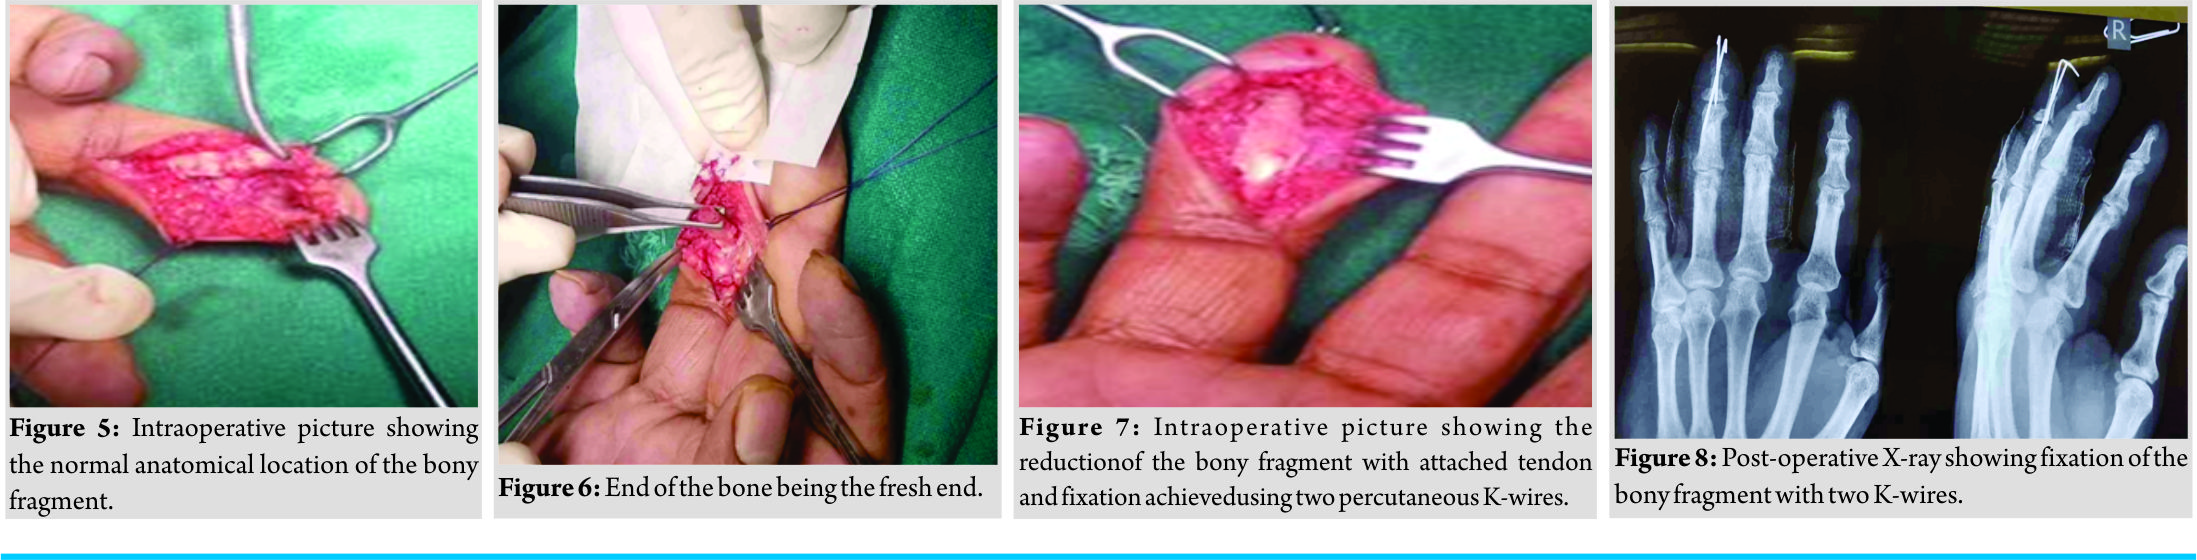

2 days after his visit, he was posted for surgery. The volar incision was used and the ring finger FDP tendon was found attached to the bony fragment. After a careful freshening of the margins, the bony fragment along with the attached tendon was reduced anatomically, and fixation was achieved using two K-wires (Fig. 3, 4, 5, 6, 7, and 8).

2 days after his visit, he was posted for surgery. The volar incision was used and the ring finger FDP tendon was found attached to the bony fragment. After a careful freshening of the margins, the bony fragment along with the attached tendon was reduced anatomically, and fixation was achieved using two K-wires (Fig. 3, 4, 5, 6, 7, and 8).  The patient was kept in a finger splint till 2 weeks when sutures were removed, and the wires were taken out at 3 weeks, and he was allowed active extension and passive flexion of the DIP joint. Gradually, he was allowed to pinch and grasp when the strength improved at 6 weeks. He was followed regularly every month initially and thereafter at 3 monthly intervals to a total of 1 year. At present, he is able to make a complete fist and is able to do all his routine activities without any difficulty (Fig. 9, 10, and 11).

Later on, a Type IV injury was described by Smith, where there is avulsion of the bony fragment and the tendon is also separated from the fractured fragment [7]. Rizis and Mahoney reported a case of FDP avulsion with an associated intra-articular fracture [8]. These types of injuries were earlier proposed by Al-Qattan as Type V injuries with further subtypes Va and Vb having extra-articular and intra-articular fractures, respectively [9]. However, in our case, the tendon was ruptured with a bony fragment of the middle one-third of the distal phalanx making it a unique pattern which has not been described earlier. Acute jersey finger injuries are usually treated operatively. In cases of chronic injuries, the preferred treatment option is chosen as per the patient requirements of the DIP function. Asymptomatic patients presenting with chronic ring finger injury can be left alone as they function well with the PIP joint flexion being preserved by the intact FDS tendon. Those requiring DIP joint function for intricate movements such as musicians are repaired with flexor tendon graft and patients who have persistent instability of the DIP joint are offered DIP joint arthrodesis [10]. In our case, the patient presented 3 weeks after the injury and he was concerned about his inability to use DIP joint function. Hence, he opted for surgical treatment. A volar surgical approach was used and FDP tendon was found to be attached to the large bony fragment, which was then anatomically reduced and fixed with percutaneous K-wires. Intraoperatively, there were no signs indicative of pathological fracture and it was concluded that the large bony fragment might be due to a broader and more distal insertion of FDP on the distal phalanx.